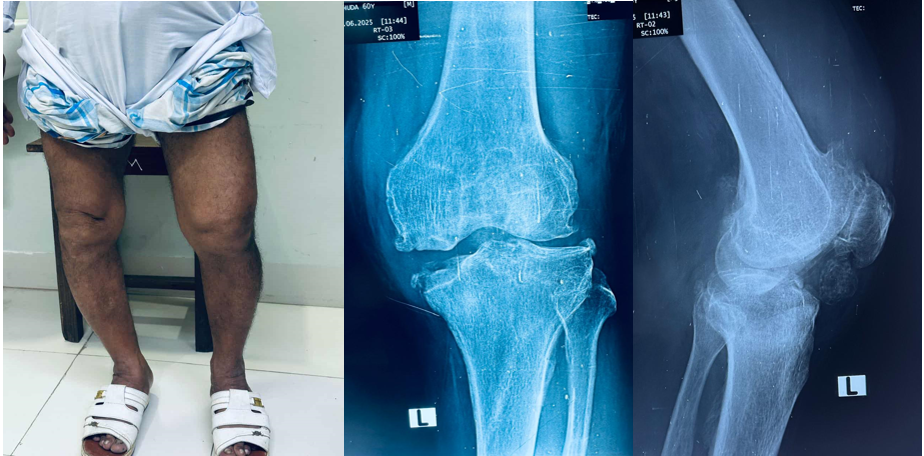

A 60 year old male with painful, deformed both knee

Before operation

Total knee replacement done on left knee on 23/06/2025